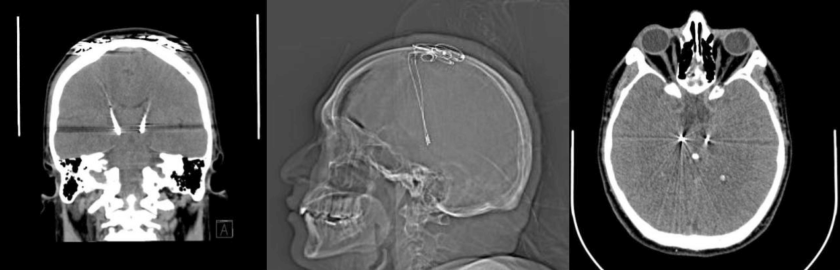

La cirugía –abreviaba DBS en inglés por deep brain stimulation– les entrega mejor movilidad a los sujetos, disminución del temblor y menor rigidez, lo que permite que personas que habían perdido independencia y oportunidades de trabajo, puedan retomar su vida. El pionero nacional en ejecutar este procedimiento fue la Clínica Alemana y su jefe de servicio de neurocirugía, el Dr. Felipe Valdivia, explica el proceso con electrodos de la siguiente manera: “En el modelo de Parkinson nosotros sabemos que cuando tú tienes Parkinson hay ciertos núcleos que están sobreexcitados. Lo que haces básicamente es inhibir esta sobreestimulación con una estimulación eléctrica de alta frecuencia sin generar lesión”.

Los especialistas describen el estimulador cerebral profundo como una especie de marcapaso que produce una alteración al nivel del circuito afectado. “Cuando uno apaga el estimulador se acaba la lesión y el paciente vuelve a estar como estaba antes. Puedes aumentar el voltaje, la cantidad de polos que se está estimulando y se mantiene al paciente mucho más tiempo porque la enfermedad sigue progresando y uno puede ir manipulando la estimulación, aumentándola”, asegura el Dr. Pedro Vázquez, neurocirujano del Hospital Clínico Universidad de Chile José Joaquín Aguirre.